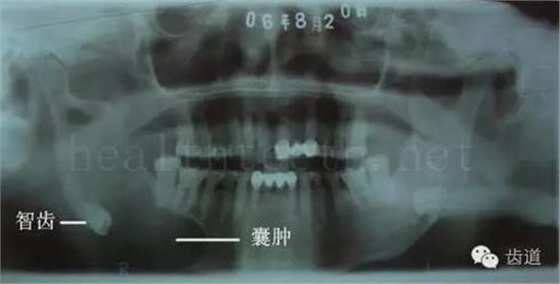

因?yàn)楸旧聿桓阏衬げ?,收集到的病例有限,大多是同事收?/span> 頰粘膜扁平苔蘚 舌粘膜扁平苔蘚 舌緣創(chuàng)傷性潰瘍 長(zhǎng)期戴活動(dòng)義齒不當(dāng)或是戴不良修復(fù)義齒造成的口腔粘膜潰瘍,應(yīng)該引起高度警惕,因?yàn)檫@種潰瘍?nèi)菀装┳?/span> 黑毛舌 舌息肉,該患者同時(shí)伴有胃、食管息肉,后來(lái)看內(nèi)科了,具體情況不詳 四、孩子的牙齒問(wèn)題 乳牙未退,牙根穿出牙齦對(duì)上唇粘膜造成刺激 乳牙滯留,也是孩子在退牙過(guò)程中最容易遇到的問(wèn)題 五、牙齒發(fā)育上的問(wèn)題 變色牙 氟斑牙 釉質(zhì)發(fā)育不全 四環(huán)素牙 牙神經(jīng)治療后的牙齒變色 10歲孩子剛剛萌出的牙齒變色 2、埋伏牙 左上乳3滯留,恒3未見萌出,曲面斷層片顯示牙齒埋伏 通過(guò)CT片確定埋伏牙齒具體的位置,顯示距離左側(cè)上頜竇很近,偏唇側(cè),這為手術(shù)定位提供了方便 手術(shù)中切斷、完整拔出,未損傷上頜竇 其他埋伏牙 3、多生牙 病例1 病例2 病例3,同時(shí)多生兩顆牙齒 4、各種畸形牙 畸形過(guò)小牙 融合牙:恒牙和乳牙都可以發(fā)生融合的情況(兩顆牙齒長(zhǎng)在了一起) 畸形中央尖:在牙齒的中央,兩個(gè)牙尖之間又多長(zhǎng)出一個(gè)牙尖,由于進(jìn)食的磨耗很容易造成磨穿,神經(jīng)就會(huì)與外界相通,出現(xiàn)牙髓炎的癥狀 六、牙齒的外傷 牙冠折斷 牙根折斷 烤瓷牙打樁修復(fù)后牙根折斷 外傷后牙齒的全脫位,應(yīng)該保留牙齒盡早做再植手術(shù) 七、牙齒的慢性損傷 牙頸部楔狀缺損 牙冠劈裂及完整拔除后的情況 牙根縱裂及拔除后的情況 牙隱裂,牙齒表面有肉眼看不到的裂紋,細(xì)菌通過(guò)其進(jìn)入牙髓,容易出現(xiàn)牙髓炎癥狀,嚴(yán)重可以造成牙齒的劈裂 這是一位來(lái)中國(guó)學(xué)習(xí)的俄羅斯大學(xué)生的牙齒,已經(jīng)做過(guò)了根管治療,牙齒咬合面有隱裂,通過(guò)鋼絲結(jié)扎固定,做鑄造金屬冠修復(fù)。 八、牙髓炎、根尖周炎 下面圖片都是慢性根尖周炎的病例,有了齲齒,進(jìn)一步發(fā)展就是牙髓炎,如果此時(shí)沒有得到及時(shí)的治療,疾病會(huì)逐漸發(fā)展破壞到根尖的骨質(zhì),將骨質(zhì)破壞后就在牙齦上出現(xiàn)一個(gè)膿瘺,此時(shí)患者不再感覺到牙齒的疼痛了,往往忽視了治療,但是這種不痛并不是疾病好轉(zhuǎn)了,而是因?yàn)榧膊〉难仔詽B出得到了引流,這個(gè)膿瘺會(huì)出現(xiàn)有時(shí)候變大了,有時(shí)候又變小了,但是如果不治療是不會(huì)自己愈合的,只有經(jīng)過(guò)完善的根管治療后才有好轉(zhuǎn)的可能,但是在疾病的治療中時(shí)間是起決定作用的,時(shí)間拖得越晚,好轉(zhuǎn)的可能性越小,經(jīng)過(guò)根管治療后如果膿瘺還是沒有消失,就需要做根尖刮治術(shù),如果仍然沒有好轉(zhuǎn),就只能做根尖切除術(shù)了,這對(duì)牙齒的穩(wěn)固是不利的。下面圖片中在膿瘺中插入了一個(gè)牙膠尖,是我們做根管充填用的材料,是非常軟的,就是在口腔牙齦瘺管的地方插進(jìn)去,通過(guò)拍牙片可以清晰地看到它到達(dá)的位置,從而確定發(fā)病的牙齒,此處是為了讓大家看得更清楚。 門牙兩個(gè)膿瘺 烤瓷牙修復(fù)后牙齦出現(xiàn)兩個(gè)膿瘺,插入牙膠尖,牙片顯示牙膠尖到達(dá)的位置就是根尖炎癥的位置,根尖骨質(zhì)密度降低(發(fā)黑的地方) 牙齒根尖膿瘺,治療前、中、后的圖片對(duì)照,完善根管治療后膿瘺明顯消失了 牙髓炎和根尖炎治療的關(guān)鍵就是根管治療 合格的根管充填治療 不良的根管充填治療 九、關(guān)于智齒(第八顆牙) 四顆長(zhǎng)不出來(lái)的智齒 智齒反復(fù)發(fā)炎造成的頰瘺,膿腫切開引流后面部會(huì)留疤 智齒造成的頜骨囊腫,手術(shù)切除后需要植骨 十、各種錯(cuò)合畸形 開合 深覆合 深覆蓋,上頜前突 反合(地包天) 牙齒排列擁擠 來(lái)源:牙醫(yī)愛看的 KQ88口腔醫(yī)學(xué)網(wǎng)